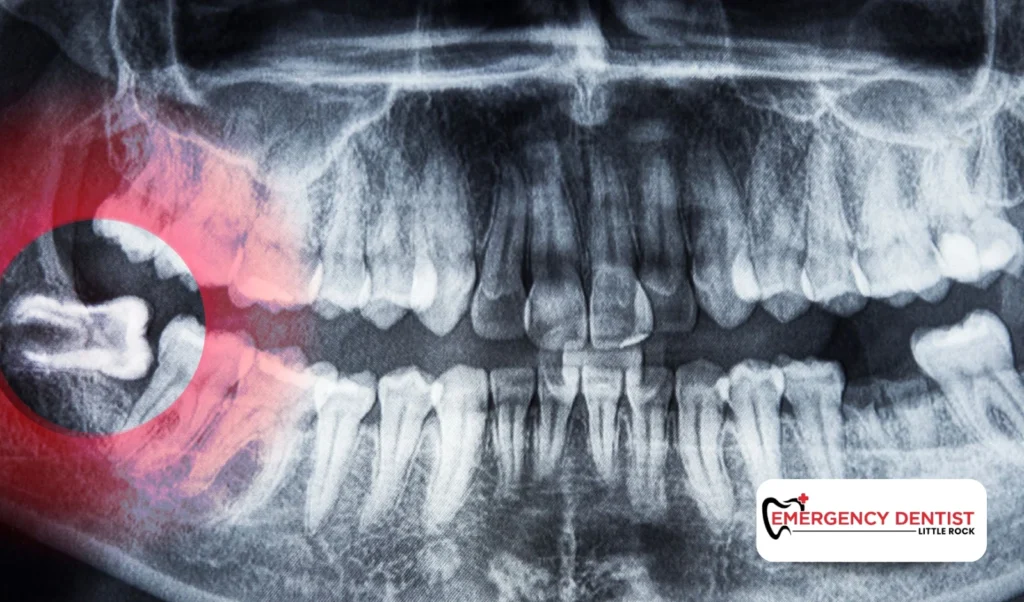

The total wisdom tooth removal cost depends on the type of extraction, whether the tooth is fully erupted or an impacted wisdom tooth, the anesthesia used, and how dental insurance plans apply. The most accurate way to understand your tooth extraction cost is through a dental exam and updated X-rays.

An impacted wisdom tooth does not fully emerge through the gums. It may grow sideways or press against nearby teeth. These situations often require oral surgery techniques and more careful planning.

Because more time and precision are involved, impacted cases often increase the average cost of a wisdom tooth removal compared to a fully erupted tooth. When people ask, how much does a wisdom tooth extraction cost, the answer often depends on whether the tooth is impacted.

• Take updated X-rays

• Determine the type of extraction needed

• Evaluate whether oral surgery is required